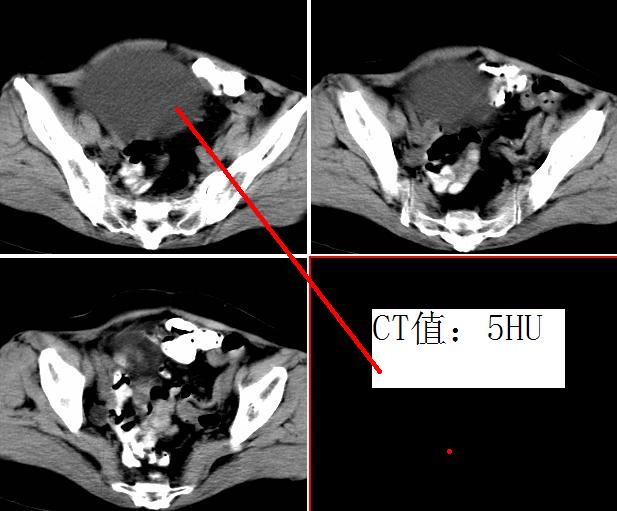

女,52岁,外伤后一小时入院,腹部b超示盆腹腔巨大无回声包块,右肾大小约208*107mm,追问病史,腹部逐渐隆8年余,无明显体重下降、消瘦、黑便呕血史,无大便性状改变,2年前已停月经,有高血压病史8年余,pe:血压180/100mmhg,全身皮肤粘膜无黄染、苍白,全身浅表淋巴结无肿大,腹部膨隆,呈蛙腹,可触及腹部有一14*15cm大小包块,质软,边界清楚,移动度可,无压痛,叩诊呈浊音。辅助检查:肝功能白蛋白43g/l球蛋白35.2g/l余指标正常,血糖电解质凝血四项正常。血常规hb115g/l白细胞13*10/9/l n0.85肾功能bun6.53mmol/l cr124umol/l.

右侧后腹膜巨大囊性肿块影阴,边缘清晰,内见膜状分隔,均匀水样密度,右肾影阴消失,囊块所到区域脏器受挤移位,右侧输尿管扩张,应该考虑:右肾重读积水,巨大肾囊肿不除外。引发肾性高血压。

腹部巨大囊性占位,膨胀性生长,边界光整,囊内容物为水样密度,其内可见多发分隔,纵观所有层面,正常右肾未见,考虑为来源于右肾的巨大多房性肾囊肿(多房性囊性肾瘤)可能性大。

腹部巨大囊性占位,膨胀性生长,边界光整,囊内容物为水样密度,其内可见多发分隔,右恻输尿管全程扩张,纵观所有层面,正常右肾未见,考虑为来源于右肾的巨大多房性肾囊肿可能性大。

反推一下:1.那么重的积水,引起积水的原因大部分是右侧输尿管有梗阻,排出受阻。右侧输尿管应该也是重度扩张才对。2.如果是肾积水,而且是右侧输尿管问题引起,那么病人肯定有相应的临床症状:比如输尿管结石引起的血尿、剧痛等症状,至少也会急性发作病史。另,本例显然不需要考虑输尿管癌,膀胱也挺好,更没有无痛性血尿病史。病人8年多没有其他的不舒服,只是腹部日渐膨隆,临床症状显然不支持。3.如果是重度肾积水的话,应该可以看到被压缩的肾皮质,即使很菲薄也多少会有显示的。